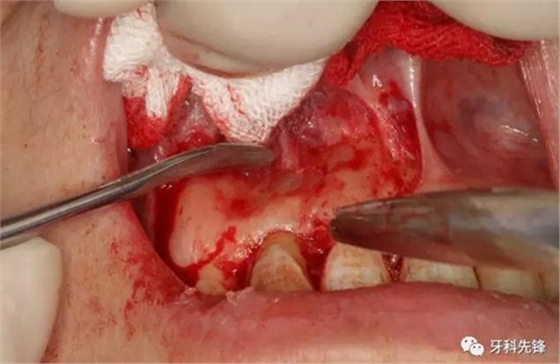

圖5.唇側(cè)梯形切口。

圖6.翻瓣、暴露術(shù)區(qū)、唇側(cè)骨板未破壞。

圖7.唇側(cè)骨板完整無缺。